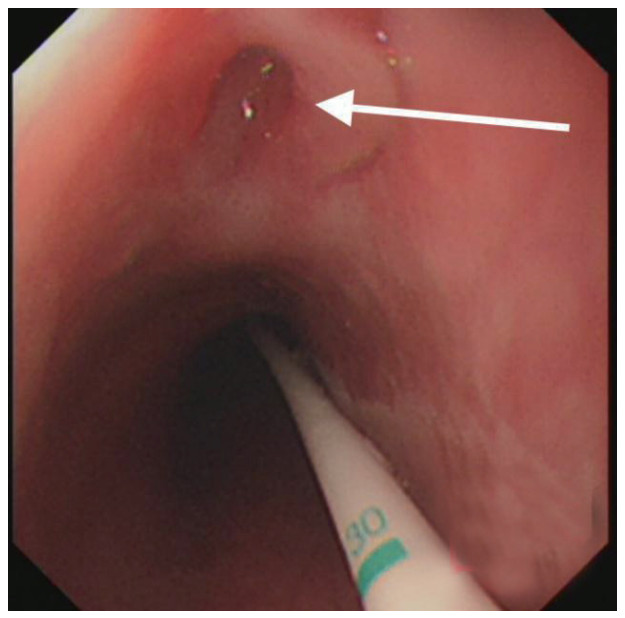

治疗经过:急诊予美罗培南0.5 g,1次/12 h抗感染,补液支持,心包引流等治疗措施,收住感染科后继续抗感染治疗,期间心包积液培养出白假丝酵母菌,加用氟康唑200 mg,1次/d, 口服,心包积液、左侧胸腔积液引流等措施,治疗10 d后复查胸部CT仍有中大量心包积液伴少许积气,纵隔积气;左侧少量胸腔积液,两肺叶间裂少许积液。对照前片(2020.10.26)心包积气及左侧胸前积液有增多,叶间裂积液新发,心包积液略有减少。右肺下叶感染,左肺下叶膨胀不全,较前右肺下叶感染有吸收,左肺下叶膨胀不全新发。考虑不能排除食管纵隔瘘,予口服碘海醇后胸部CT检查(图 3~6):约胸6椎体水平食管纵隔瘘,瘘口为相应水平食管壁右前方可能;胃镜(图 7):食道距门齿25 cm右后壁见一直径约1.0 cm凹陷,内有一小瘘口。胃镜下予钛夹2枚夹闭瘘口(图 8),同时植入空肠营养管。至此患者病情明确诊断食管心包瘘,患者经以上治疗后心包积液、胸腔积液逐渐减少,于11月13日拔除心包及胸腔引流管,因患者签字回当地就诊,予口服莫西沙星、氟康唑带药出院,出院后随访,患者未回当地医院治疗,仅在家中继续空肠营养管饲喂及口服抗菌药物治疗。

图 7 箭头所指为食管瘘瘘口,同时可见空肠营养管